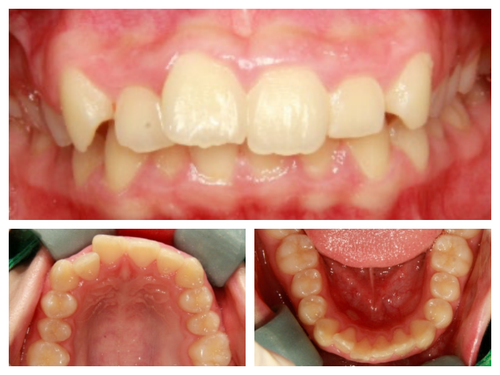

무대에 서는 친구들이라 외모에 민감하고 특히 돌출과 비대칭때문에 사진 찍을 때 신경이 많이 쓰인다고 했다.

사실 골격적인 비대칭이 심해서 교정이 끝나도 비대칭이 남겠지만 돌출이 개선되면 훨씬 예뻐질것이기에 과감히 발치를 하고 좌,우 최대한 중심선을 맞추면서 교정을 끝낸 케이스

웃을때 잇몸이 많이 보이고 입이 나온것 같아 신경이 쓰인다던 발레리나

네 개의 소구치를 발치하고 교정을 시작했다.